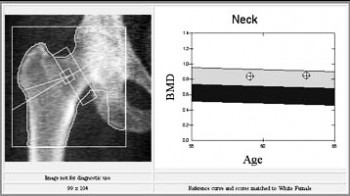

"Zlatni standard" i jedina pouzdana metoda o tkrivanja osteoporoze je koštana denzitometrija-mjerenje koštane gustoće (koštane mase). Najsuvremenija tehnika zasniva se na "metodi dexa" koja koristi rendgenske zrake dviju različitih energija, a pokazuje gustoću minerala u kosti izračunatu u gramima na četvorni centimetar. Metoda je potpuno bezbolna, nije potrebna nikakva posebna priprema, normalno možete jesti i piti, te popiti terapiju koju inače uzimate, prije pregleda. Takodjer, možete se obući kako želite ali bez metalnih dijelova, dugmadi, kopči… Pretraga je jednostavna i brza, traje 5-10 minuta. Doza zračenja primljena pri denzitometriji tako je mala da se ni osobe koje rade s uređajem ne štite posebno i iznosi 1-3 mRem, što odgovara dozi zračenja koja se primi tijekom leta avionom u trajanju 3-9 sati ili na površini Zemlje od kozmičkog zračenja u trajanju od 3-9 dana. Za usporedbu, pri rengenskom snimanju pluća prosječna doza zračenja je 300 mRema. Prosječna doza zračenja na površini Zemlje koju ljudi godišnje prime iznosi oko 400 mRema

Rentgensko snimanje kostiju nesigurna je i neprecizna metoda. Greška u procjeni koštane mase je 30-50%. Na osnovu ove pretrage pouzdano se postavlja dijagnoza osteoporoze tek kod gubitka koštane mase većeg od 30-40%. Na osnovu gustoće kosti (mjeriti će se lumbalna kralješnica i bedrena kost / kuk) ljekar će moći procijeniti u kakvom su stanju Vaše kosti (tj. radi li se o osteoporozi ili ne) i preporučiti Vam daljnje postupke, odnosno najbolju terapiju za Vas.